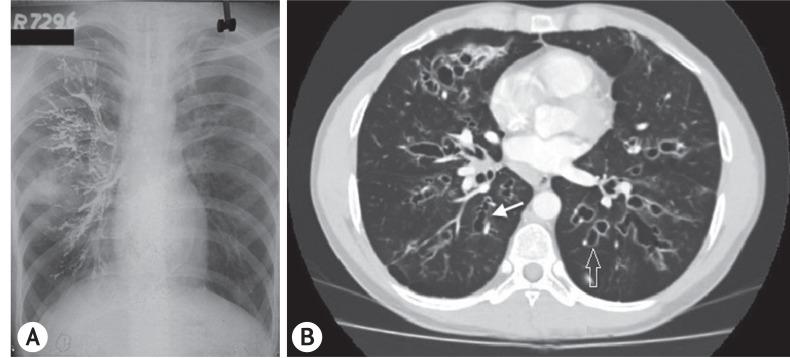

This retrospective review documents the occurrence of pediatric ABPA over a period of 31 years in one unit. Children with asthma, eosinophilia and infiltrates on chest radiograph were screened for ABPA. In these patients, demonstration of immediate hypersensitivity response against species along with serological profile and pulmonary function testing were done. Bronchography/computed tomography (CT) of the chest demonstrated central bronchiectasis (CB). CT of the paranasal sinuses was done in patients with upper airways symptoms. In those suspected with allergic sinusitis (AAS) consent was sought from the parents for the invasive procedure needed for the diagnosis of AAS.

Of the 349 patients with ABPA diagnosed, 42 (12.03%) were in the pediatric age group. The mean age on presentation was 12.9 ± 4 years with a male preponderance. All patients had asthma and positive intradermal/skin prick test against species. Ring shadows, the most common radiological presentation, were seen in 28 of 42 patients. Bronchography/CT of the chest demonstrated CB, a feature pathognomic of ABPA, in 32 of 42 patients. High attenuation mucus plugs was observed in 7 of 36 patients while ABPA-seropositive was diagnosed in 10 of 42 patients. On imaging, sinusitis was seen in 20 of 30 patients with upper airways symptoms of whom eight had suspected AAS. Three parents consented for surgery, which confirmed the diagnosis.